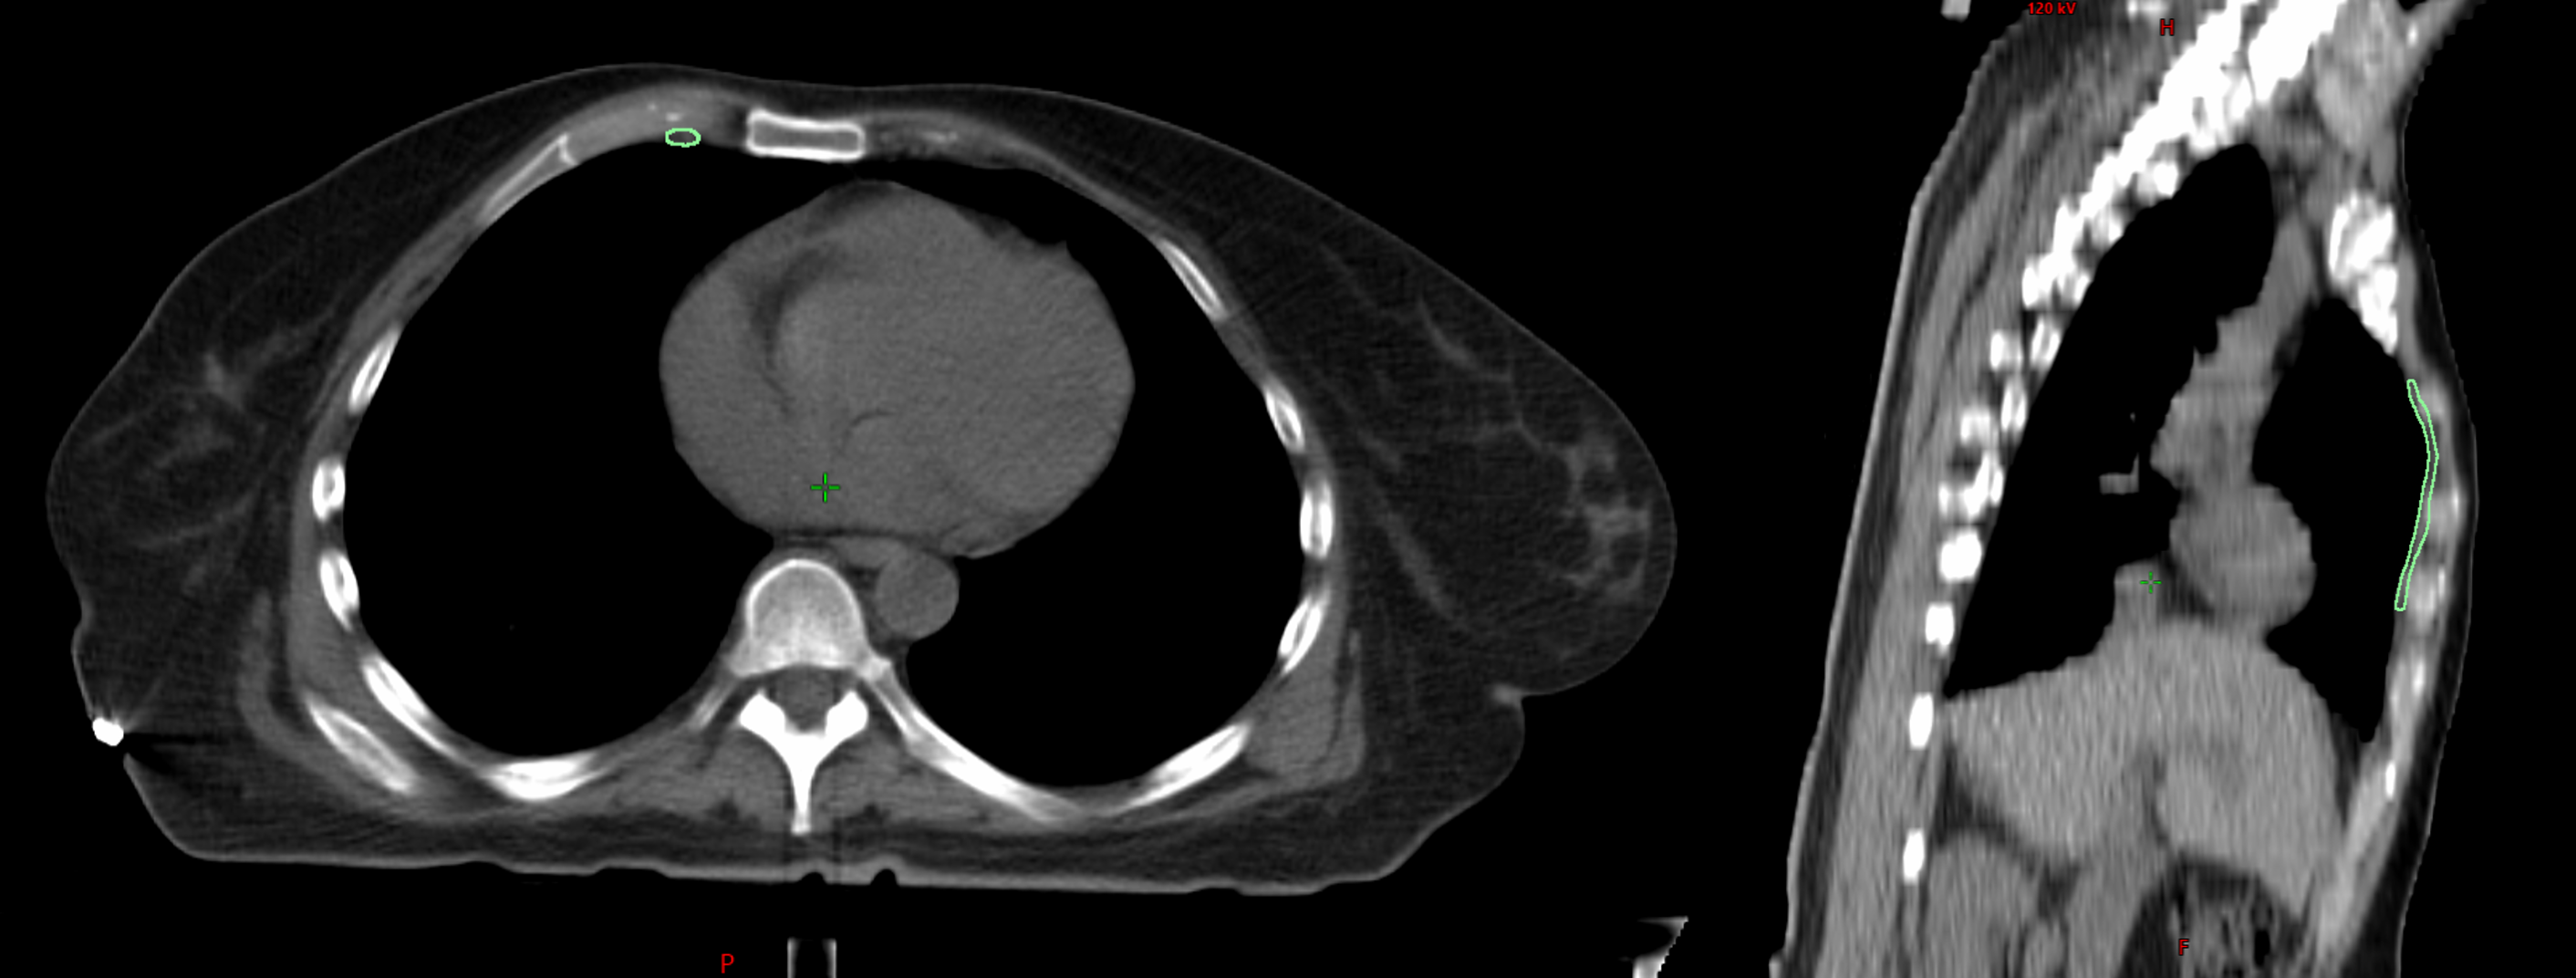

Breast cancer can spread to the internal mammary lymph nodes (IMNs), located near the center of the chest. When involvement is confirmed, IMN irradiation (IMNI) can improve outcomes; however, its use in low-risk patients remains controversial due to potential radiation exposure to the heart, lungs, and contralateral breast. This project contributes to a retrospective population study at BC Cancer investigating how primary tumor location and IMN radiation dose relate to survival outcomes. To support this research, a data pipeline is being developed to automate the import and segmentation of approximately 19,000 patient CT datasets (2005–2014) using Limbus Contour, a deep learning-based auto-segmentation software. My contributions include developing C# scripts for contour transfer and a QA system to evaluate the accuracy of AI-generated contours for future pipeline integration.

In-house scripts were written in C# using the Eclipse Scripting API (ESAPI) to analyze contour quality. The QA tool flagged patients with contours outside of statistically defined ranges (median ± 2SD, Min/Max, IQR) or with structural faults such as missing slices.

- Method B: Compared AI contours to a reviewed subset of 100 Limbus-generated contours (RTOG guideline), providing a consistent baseline.